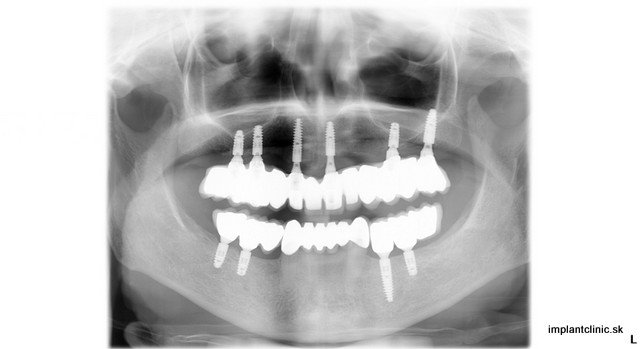

Takto sa vyjadrila o Implant Clinic Vendy. Podstúpila zákrok, ktorý vyžadoval dvojitú dostavbu kosti, 10 zubných implantátov a 24 implantátových koruniek. Ak zuby chýbajú dlhšiu dobu môže dojsť k úbytku kosti. Resorpciou kosti strácajú mäkké tkanivá oporu, čím môže Vaša tvár nadobudúť starší vzhľad.

Umiestnením zubných implantátov do čeľustnej kosti predchádzame tomuto procesu, pretože podobne ako Vaše vlastné zuby aj zubné implantáty prenášajú žuvacie sily na okolitú kosť, čo ju stimuluje a tým sa predchádza úbytku kosti. V niektorých prípadoch ako u Vendy bola potrebná dostavba kosti. Mnoho ľudí má mýlnu mienku o tomto zákroku a myslia si, že je to zložitý proces.

Dostavba kosti vôbec nie je zložitý chirurgický zákrok. Je bežne robený len za pomoci lokálnej anestézy. Po zákroku pacient môže hovoriť. Strava by mala byť upravená na mäkkú alebo na tekutú, aby sa neporušili stehy a rana sa pekne zahojila. V prípade bolesti môžete užiť lieky od bolesti. Pacient môže ísť na druhý deň do práce. Toto ošetrenie sa nazýva aj augmentácia kosti. Dostavba kosti slúži na obnovu strateného kostného tkaniva. Augmentácia sa používa pri relatívne malých defektoch kostí. Cena a priebeh sa dá určiť až po dôkladnom vyšetrení pri osobnej konzultácií.